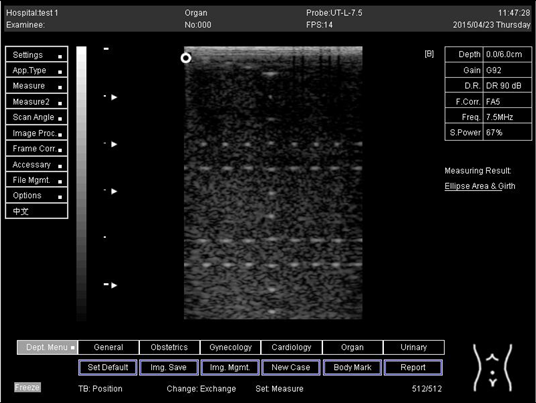

9.0 Axial resolution

Biomimetics 07 00130 i001

D1 = 4.9

D2 = 4.1

D3 = 3.1

D4 = 2.2

Lateral resolution

Biomimetics 07 00130 i002

D1 = 5.0

D2 = 4.0

D3 = 3.0